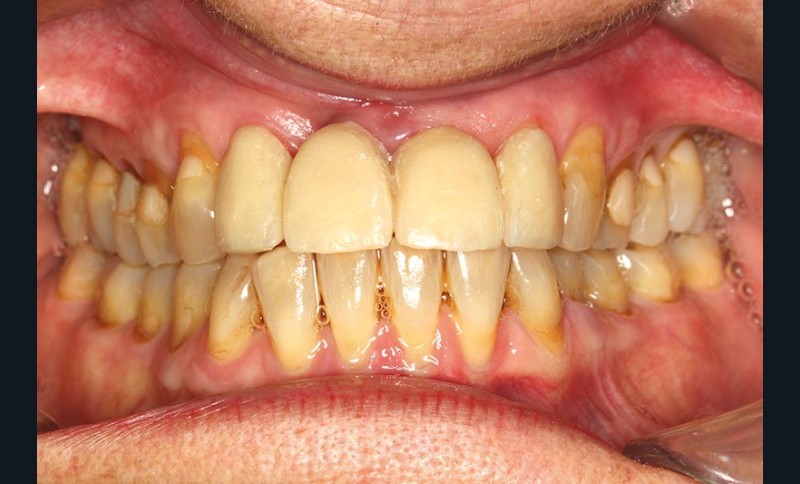

Un montage en articulateur des moulages permet d’observer en relation centrée (RC) de meilleures conditions d’affrontement des dents antérieures. La proposition thérapeutique est la réfection du bridge existant, une équilibration occlusale par coronoplastie des secteurs postérieurs pour stabiliser les appuis occlusaux en RC et la mise en place d’une contention dans le secteur antérieur mandibulaire. Une maquette prothétique permet la réalisation d’un bridge provisoire dans une position corrigée (fig. 4).